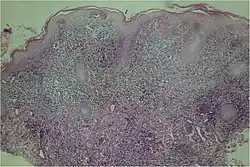

Lesion biopsy under a microscope, clear epidermal hyperplasia

A microscopic examination of a biopsy of a yaw may show skin with clear epidermal hyperplasia (a type of skin thickening) and papillomatosis (a type of surface irregularity), often with focal spongiosis (an accumulation of fluid in a specific part of the epidermis). Immune system cells, neutrophils and plasma cells, accumulate in the skin, in densities that may cause microabscesses.

Warthin–Starry or Levaditi silver stains selectively stain T. pallidum, and direct and indirect immunofluorescence and immunoperoxidase tests can detect polyclonal antibodies to T. pallidum's. Histology often shows some spatial features that distinguish yaws from syphilis (syphilis is more likely to be found in the dermis, not the epidermis, and shows more endothelial cell proliferation and vascular obliteration).[2]